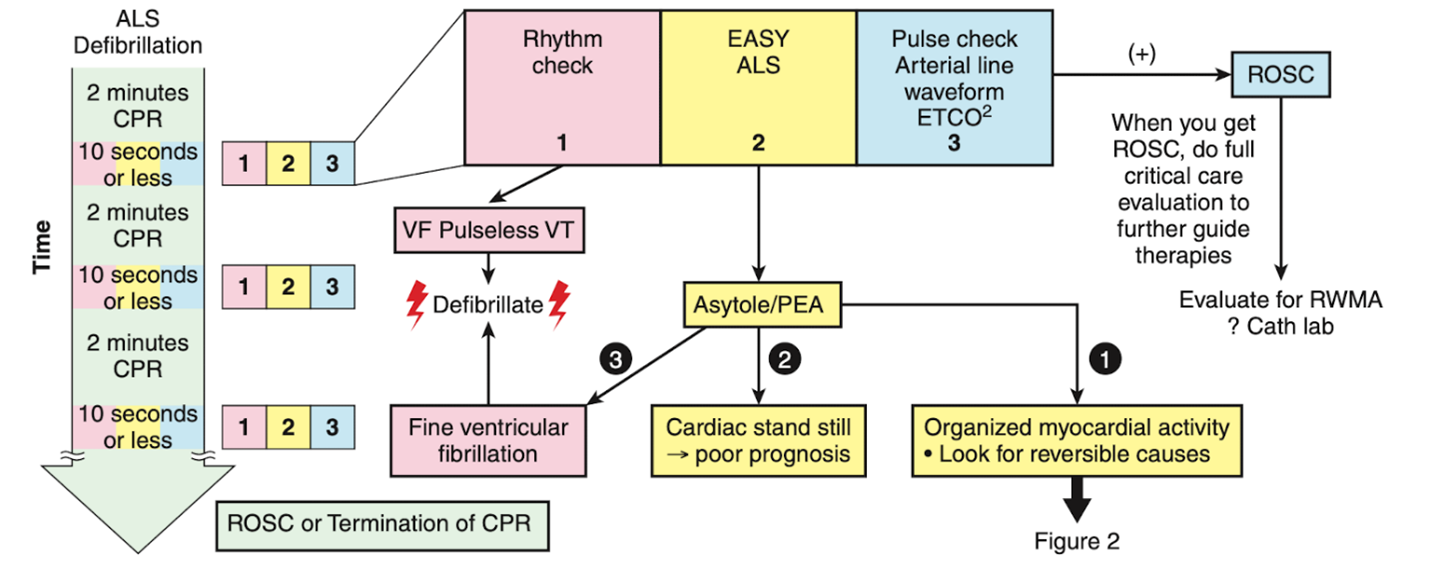

To shorten the duration of interruptions in CPR, protocolized approaches to use ultrasound were developed.15-22 After the introduction of the protocols, the length of CPR interruptions uniformly decreases, although often not to below 10 seconds. With no evidence to support one approach over others, we would like to highlight the EASy-ALS protocol (outlined in Table 1, Figures 1 and 2, and Video 9). The EASy-ALS protocol is the protocol utilized by anesthesiology residents during IHCA.22 This protocol calls for prerequisite training including simulation, which focuses on teamwork, communication, high-quality CPR, and limiting pulse/rhythm checks to fewer than 10 seconds. In our experience, simulation-based training results in consistent shortening of interruptions in CPR during simulated cardiac arrest.23

Figure 1. Algorithm for the use of EASy-ALS. This algorithm incorporates FOCUS into the ≤10-s pulse/rhythm check of CPR. A systematic approach allows identification of a shockable rhythm if present and completion of EASy-ALS to search for a cardiac cause of the event without holding chest compressions for >10 s. (Used with permission from N. Bughrara, MD, Albany, NY.) CPR indicates cardiopulmonary resuscitation; EASy-ALS, echocardiographic assessment using subcostal-only view in advanced cardiac life support; FOCUS, focused cardiac ultrasound; PEA, pulseless electrical activity; ROSC, return of spontaneous circulation; RWMA, regional wall motion abnormality; VF, ventricular fibrillation; VT, ventricular tachycardia.

The responding resident is alerted to an acutely decompensating patient in the SICU or medical or surgical ward by direct call from the primary service or by overhead Code Blue page. On arrival, the resident prepares to serve as a sonographer and complete an EASy-ALS exam. The ultrasound probe is placed in the subcostal window before the pulse/rhythm check without obstructing chest compressions. The code leader, a senior primary care team provider, is responsible for holding and resuming chest compressions. The code leader assigns a nurse to count down 10 seconds during the pulse/rhythm check; this is standard at our institution. After resumption of chest compressions, the resident interprets recorded images and communicates findings to the code leader. The primary phenotypes (Figure 2) to be identified are cardiac standstill (see Video 1), pericardial effusion (Video 2), dilated right ventricle (RV) (Video 5), dilated left ventricle (LV) (Video 6), and underfilled heart (Video 7). The resident can obtain extracardiac views (such as the subcostal IVC View, Video 3), between pulse/rhythm checks.